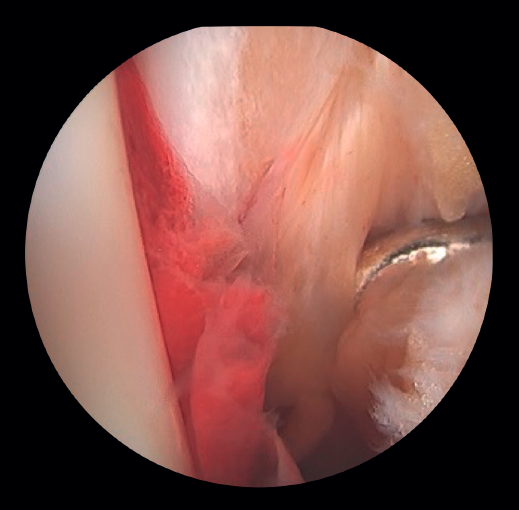

- Management of chondral injuries. The literature reports the presence of chondral injuries in 34-91% of all ankle fractures. These lesions are frequently located in the talus and are most common in severe fractures, such as Weber C and PER fractures. Patients with cartilage lesions were 3.5 times more likely to develop radiographic osteoarthritis (Kannus arthritis score < 90) and 5 times more likely to have an unfavorable long-term clinical prognosis (American Orthopedic Foot and Ankle Society [AOFAS] score < 90)(14).

If possible, we reinsert unstable osteochondral fragments (Figure 3). In chondral lesions where it is not possible to reinsert the fragment, cartilage repair stimulation techniques can be used(5,13).